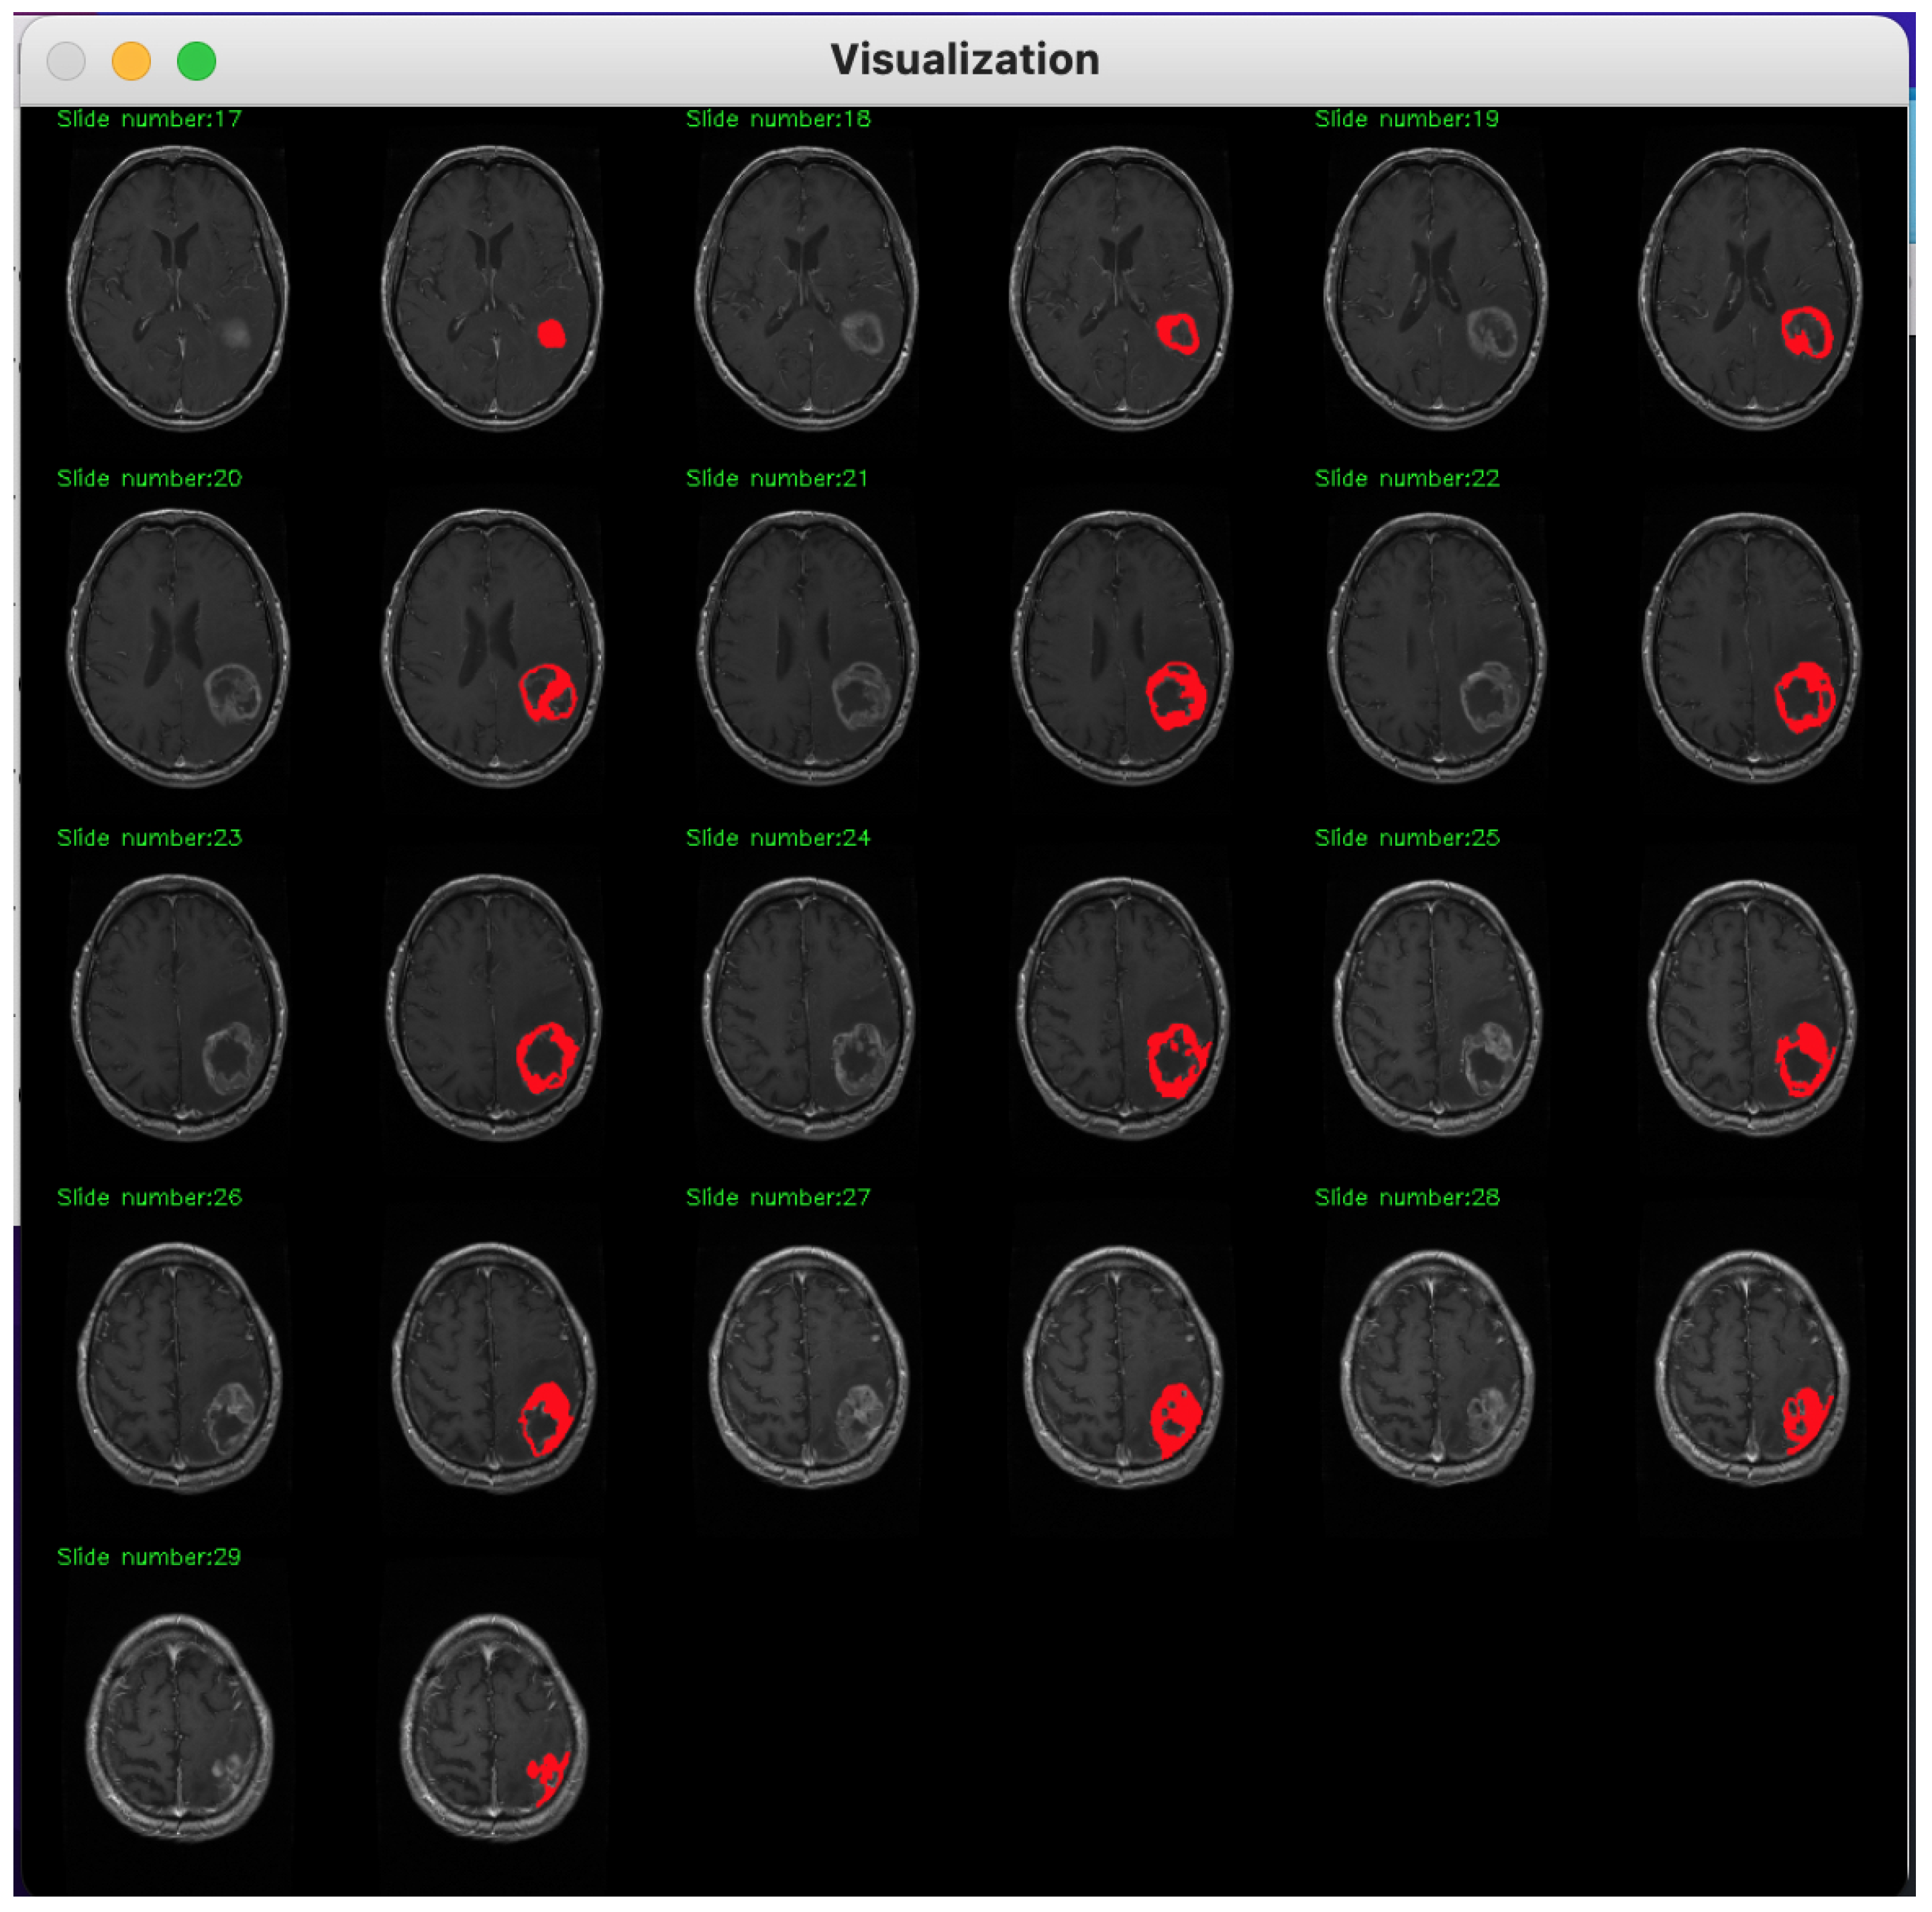

2. Method Description

3. Database Description

4. Experimental Assessment